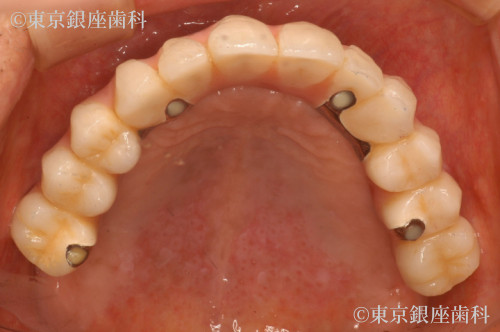

重度歯周病、義歯不適合による咬合障害をワンデイインプラントで改善した症例

After

全体的に歯周病が進行していること、咬合改善を希望されていることから残存歯を全て抜歯してワンデイインプラントにすることにした。